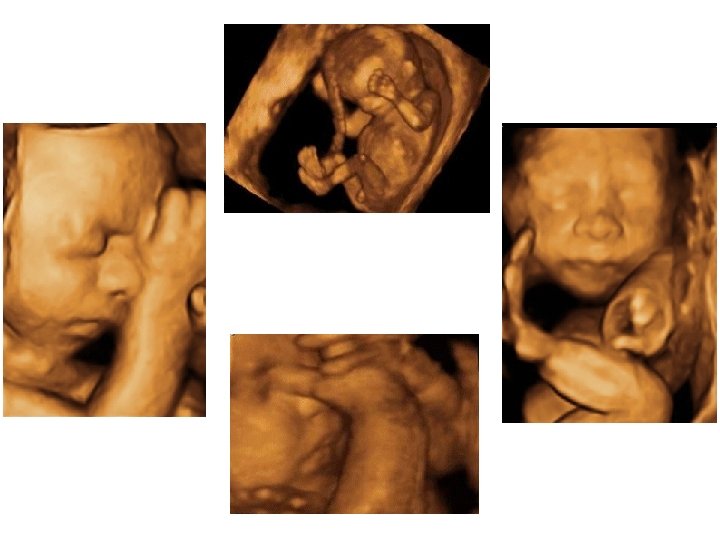

Matériel et équipement • Échographe multisondes - Sonde abdominale de 3, 5 à 5 MHz - Sonde vaginale de 5 à 7, 5 MHz • Un doppler pulsé à codage couleur • Mode 3 D pour l’acquisition d’un volume écho dont le traitement informatique peut extraire tous les plans de coupe souhaités (face, extrémités ++)

• Étude morphologique approfondie - pôle céphalique : contours de la boite crânienne, volume des ventricules latéraux, structures de la ligne médiane, cervelet (aspect et mesure de sa largeur) - distance inter-orbitaire - coupe nez-lèvre - profil : menton aligné avec le front, mesure des OPN

- thorax : cœur (position, 4 cavités équilibrées, septum inter ventriculaire, croisement Ao/AP), poumons - abdomen : paroi intègre, estomac (position, volume), vésicule biliaire, intestin grêle - arbre urinaire : vessie (position, volume), 2 reins - sexe - rachis avec son revêtement cutané - membres : 4 x 3 segments, 5 doigts aux 2 mains, mouvements d’ouverture des mains, mesure du pied